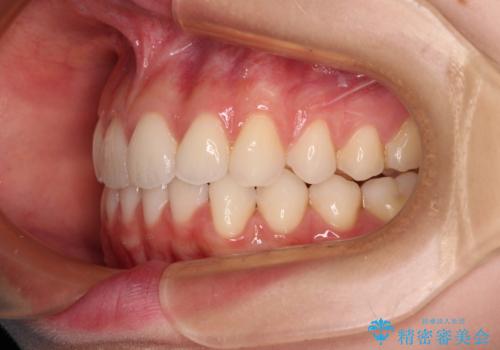

前歯のデコボコと深い咬み合わせ インビザラインできれいに改善

- 前歯のデコボコと下の前歯が隠れてしまう咬み合わせを気にして来院された患者様です。

インビザラインによる上下歯列の拡大と、IPR(歯と歯の間を削る)にるスペースの獲得により、口元のデコボコとディープバイトを改善することとしました。

インビザラインは、装着していない時間がどれだけ短いかが、治療期間を大きく左右します。こちらの患者様は1日22時間以上、毎日欠かさず装着してくださったため、1年弱という短期間で満足のいく歯列に整えることができました。